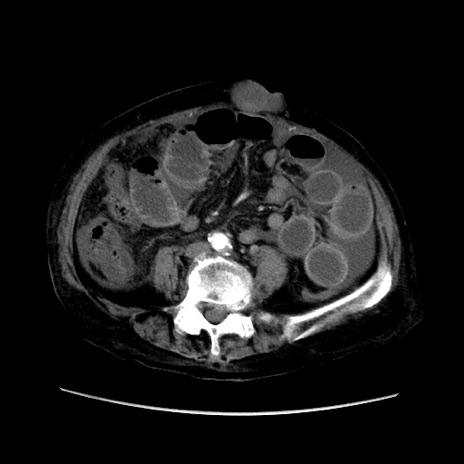

症例31(横断像)

【症例】80歳代 女性

【主訴】腹部膨満感

【現病歴】他院にて肝硬変にてフォロー中。1週間前から便秘、腹部膨満感、臍部腫瘤あり受診となる。

【既往歴】肝硬変

【身体所見】腹部膨隆あり、皮膚変化なし、疼痛なし。

【データ】WBC 4600、CRP 0.25